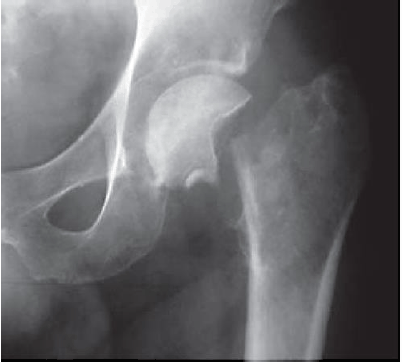

A imagem abaixo caracteriza: